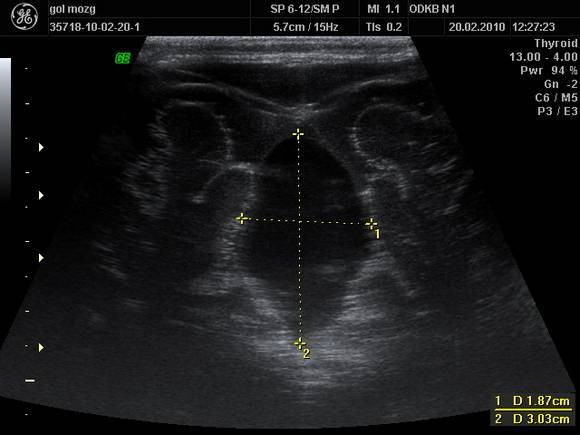

Нейросонография (или ультразвуковое исследование новорождённых) в последнее время стала обычной рутинной процедурой, применяемой в отношении всех без исключения детей в первые дни и месяцы их жизни. Этому есть вполне логичное объяснение: на настоящий момент такое узи мозга новорождённых признано самым безопасным, безболезненным и очень информативным способом всестороннего анализа головного мозга малыша, этот метод позволяет заблаговременно принять все необходимые меры для излечения при выявлении болезней или патологии.

УЗИ-анализ головного мозга младенца может выявить определённые патологии, перечисленные ниже. В то же время этот метод не позволяет распознать заболевания, в основе которых — гормональные, генетические или биохимические нарушения, так как при этом структура головного мозга не изменяется. Следует также учесть, что нейросонография — лишь один из способов получения всесторонней информации о состоянии здоровья малыша и не может быть исчерпывающим. Иногда возможны спорные мнения по поводу замеченных при узи изменениях в головном мозге ребёнка. На данный момент врачам удаётся распознать с помощью узи головного мозга такие болезни и патологии у новорождённых:

В ходе проведения нейросонографии головного мозга новорожденных специалист получает необходимую для оценки состояния головного мозга информацию.

Показатели нормы выглядят следующим образом:

- Новообразования не выявлены;

- Мозговые структуры симметричны;

- Мозжечок симметричен и имеет трапециевидную форму;

- Сосудистые сплетения характеризуются однородностью;

- Желудочки мозга однородны и симметричны;

- Борозды и извилины органа четко визуализируются;

- Жидкости в щели между полушариями не выявлено.

При проведении нейросонографии у новорожденных специалист может обнаружить различные патологические изменения. Наиболее часто во время НСГ выявляют следующие отклонения:

- ассиметрия мозговых полушарий, связанная с появлением в мозге объемных образований — опухолей, кист и др.;

- гиперэхогенные округлые структуры, расположенные в глубине головного мозга или рядом с мозговыми оболочками. Они соответствуют кистам, заполненным ликвором;

- увеличение объема желудочков и уменьшение толщины мозговой ткани характерно для гидроцефалии. Заболевание сопровождается ростом внутричерепного давления и сдавлением головного мозга;

- аномалии развития различного строения.